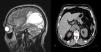

Nine months later, the patient presented visual disturbances and vertigo. Magnetic resonance imaging of the head with contrast medium was performed and a single tumor lesion was found in the left temporal lobe (Fig. 1, right panel). Metastasectomy with adjuvant radiotherapy was performed. Five months later, abdominal tumoration of the right adrenal gland was detected on an abdominal ultrasound (Fig. 1, left panel), confirmed on a CT scan with contrast. Adrenalectomy was performed. The patient is currently in follow-up, 5 years after the last procedure.